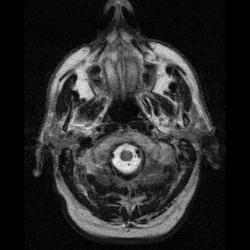

O campo da neurotecnologia existe desde a primeira metade do século XX, mas tornou-se maduro somente em meados da década de 1980. A representação do cérebro por imagens revolucionou a área e estimulou o início de várias pesquisas visando o monitoramento direto de áreas do cérebro durante a realização de experimentos. De medicamentos farmacêuticos à varredura cerebral, a neurotecnologia passou a afetar diretamente a qualidade de vida da população de forma direta ou indireta, seja pelo uso de drogas como antidepressivos ou de exames da atividade cerebral.[2]